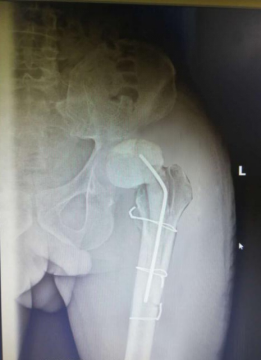

经过一段时间的康复和观察, 2020年4月23日,张先生再次入院,我院骨科汪军、何涛、吕彬林三位医生通力合作为张先生行“关节翻修术”。手术中将张先生左侧的人工髋关节间隔器取出,取除旷旷置骨水泥假体,并按生理角度安放人工髋关节。手术用时月2个小时,患者顺利完成了手术并被送回病房,术后患者恢复良好,并于2020年5月18日出院。

手术前的X光成像

安放骨水泥旷置器后

人工关节翻修后